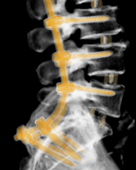

Im Zentrum für Wirbelsäulenchirurgie und Schmerztherapie wird das gesamte Behandlungsspektrum bei Erkrankungen, Unfällen und Schmerzsyndromen der Hals-, Brust- und Lendenwirbelsäule sowie der angrenzenden Strukturen bei Kindern und Erwachsenen in interdisziplinärer Vorgehensweise abgedeckt. Rund um die Uhr besteht die Möglichkeit der Maximalversorgung. Häufig erfolgt die Therapie nach einem Stufenschema, bei dem versucht wird, mit weniger eingreifenden Maßnahmen zu beginnen. Je eingreifender die Therapie, umso höher ein theoretisches Risiko des Auftretens negativer Nebeneffekte.

Insgesamt steht die Behandlung von Verschleißerkrankungen im Vordergrund. Des Weiteren werden im Zentrum jegliche Arten von z. B. Unfällen, Infektionen, Tumoren und Metastasen, Deformitäten, rheumatischen und angeborenen Erkrankungen bei Erwachsenen und Kindern behandelt. Jährlich erfolgen neben den konservativen mehr als 15.000 interventionelle Maßnahmen sowie mehr als 3.000 Operationen. Wenn möglich werden minimalinvasive oder bewegungserhaltende Verfahren angewendet.